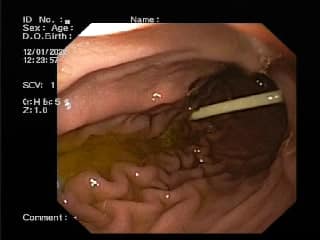

Родителям предложили сделать диагностическую гастроскопию. Поэтому палочку вытянули, она имела длину 8 сантиметров.

В Днепре ребенок съел палочку от конфеты Chupa Chups (facebook.com/groups/Дитячий эндоскопический центр)